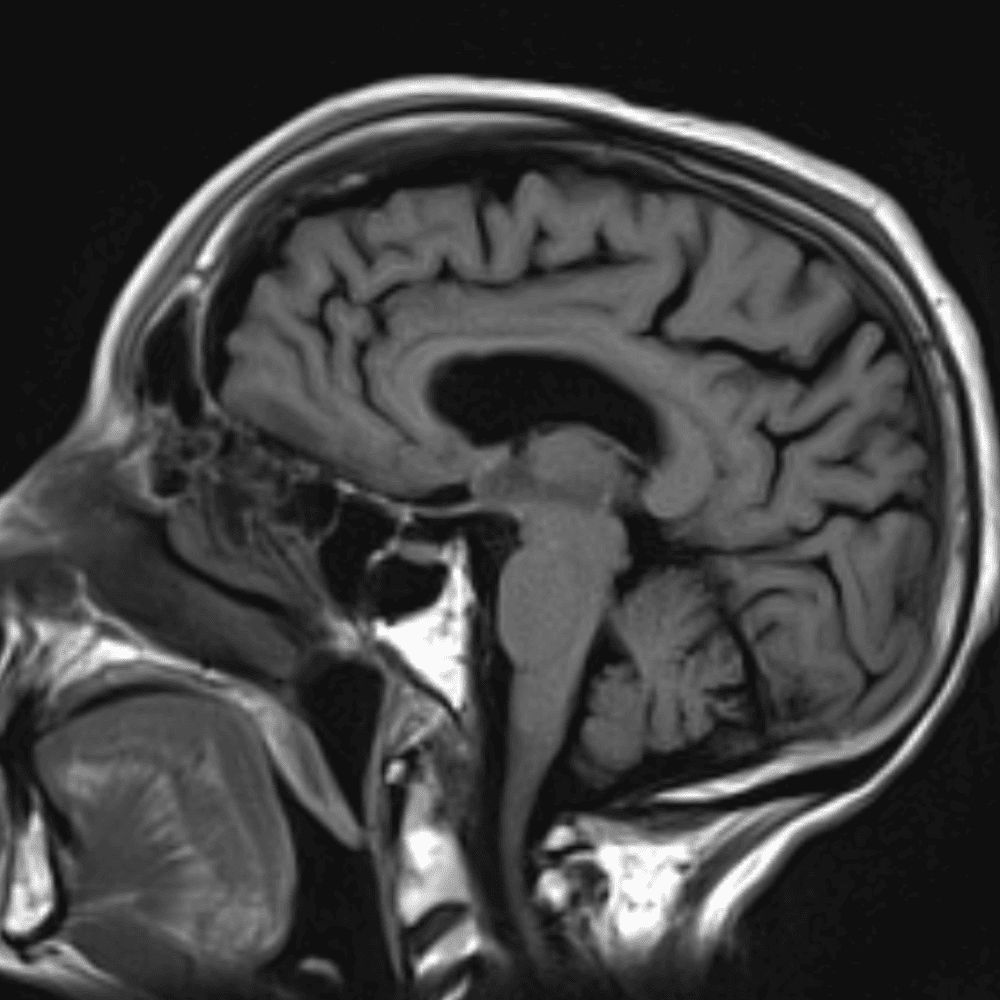

๋‹น์ง ์‹œ ํ”ํžˆ ๋ณผ ์ˆ˜ ์žˆ๋Š” ์‚ฌ๋ก€์˜ ์ „ํ˜•์ ์ธ ์˜ˆ๋ฅผ ํฌํ•จํ•ฉ๋‹ˆ๋‹ค.

39 ์‚ฌ๋ก€